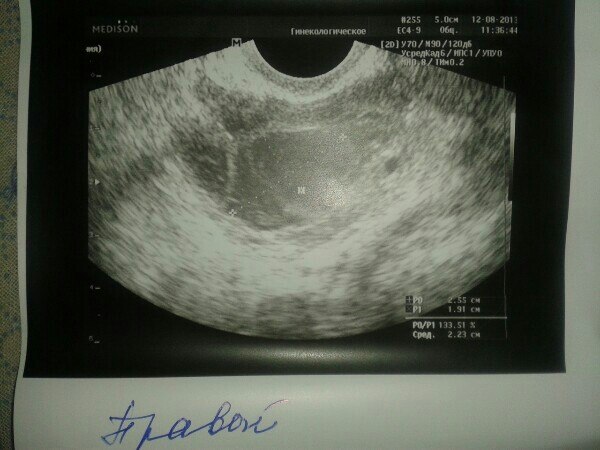

Девчоки. Я в мае перенесла лапару на поликистоз. В прошлом месяце в пр.яичнике были 2 фоллика, из которых 1 перерос. В левом ничего не было((( Вчера на 10ДЦ на узи врач увидела вот такую картину. в правом киста, а в левом переросший фоллик. И опять не назначила мне укол ХГЧ для стимуляции. Сказала прийти к ним на узи на 3-5 ДЦ в след.цикле. А сегодня появилась боль в районе правого яичника. Девочки, я уже отчаилась. Так жутко на сердце((( Неужели я не смогу забеременеть.